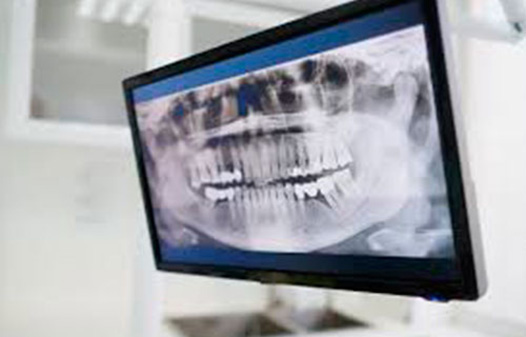

RADIOLOGIA ODONTOLOGICA

Se trata de una radiografía panorámica dental que brinda una imágen completa y única a la vez de dientes, maxilares y mandíbula.

Y ofrece una visión general, aporta información vital para determinar las dolencias que afectan y los tratamientos odontológicos que habrá que llevar a cabo.

● Ortopantomografía